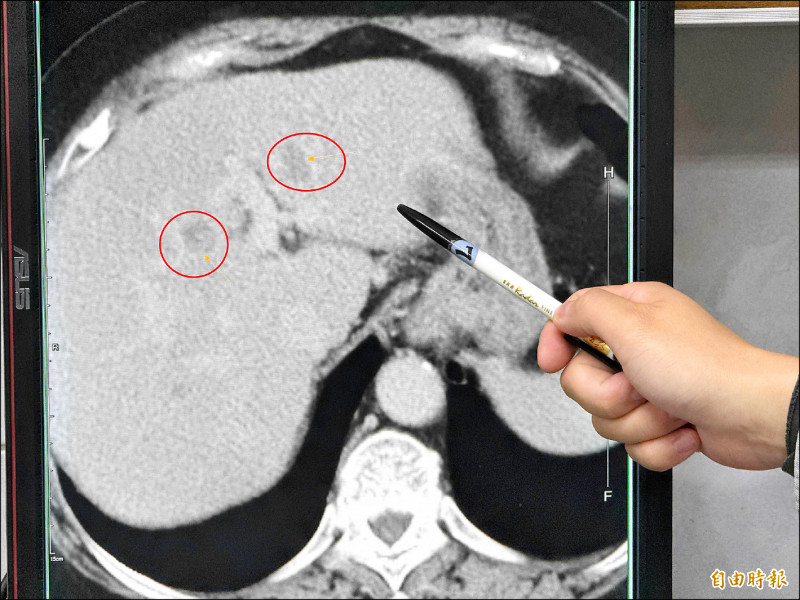

嗜吃甜食的「螞蟻人」要注意!台中1名60多歲的婦人,日前到醫院就診意外發現有嚴重的脂肪肝及疑似腫瘤,進一步詳細檢查,在左邊肝臟看到2顆腫瘤,安排手術治療,醫師手術時驚覺,婦人脂肪肝居然佔肝臟的4到6成以上,術後追問,患者本身沒有喝酒習慣,也沒有B、C肝炎,但是平時很喜歡吃甜食、水果,導致產生重度的代謝異常脂肪肝,甚至病變成肝癌。

駐診在李綜合醫院的台中榮總一般外科醫師吳坤達表示,婦人在門診腸胃科做超音波時,發現有重度脂肪肝及疑似腫瘤。進一步檢查確認在肝臟的左外側葉及左葉中部各有1顆腫瘤,擔心把患者左邊肝臟全切除後,患者肝臟功能恐無法運作,因此,使用「類機械手臂」多關節器械系統切除左外側肝葉,及術中射頻消融治療術消除腫瘤。

吳坤達說,即使是肝完全健康的年輕患者,肝臟切除手術至少要保留1/3,才能維持基本生理功能。該名患者有4到6成脂肪肝,又有多顆腫瘤,為了讓她的肝臟能正常運作,脂肪肝切下了223克,大約1顆小蘋果的重量,沒有切除的腫瘤則採用射頻消融治療術讓組織壞死,手術進行大約3個多小時,失血量僅有約400c.c.,患者術後恢復良好。